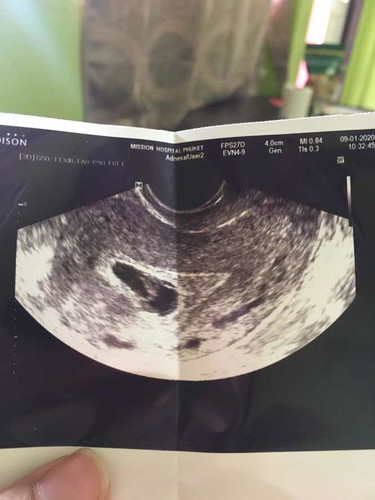

รบกวนสอบถามหน่อยคะ. พอดีมีเลือดสดออก แต่ไม่ปวดท้อง. พอไปหาหมอ. หมอ อันต้าซาว ก็บอกว่านอกรกมีแต่เลือด. มีแม่คนไหนเคยเป็นเปล่าคะ. แล้วสุดท้ายแท้งเปล่าคะ ตอนนี้8 สัปดาห์

พอดีหมอบอก ยังไม่ได้ยินเสียงหัวใจคะ กลางวันไม่มีเลือดคะ. แต่พอตกกลางคืน20:00ก้อจะมีเลือดออกคะ.